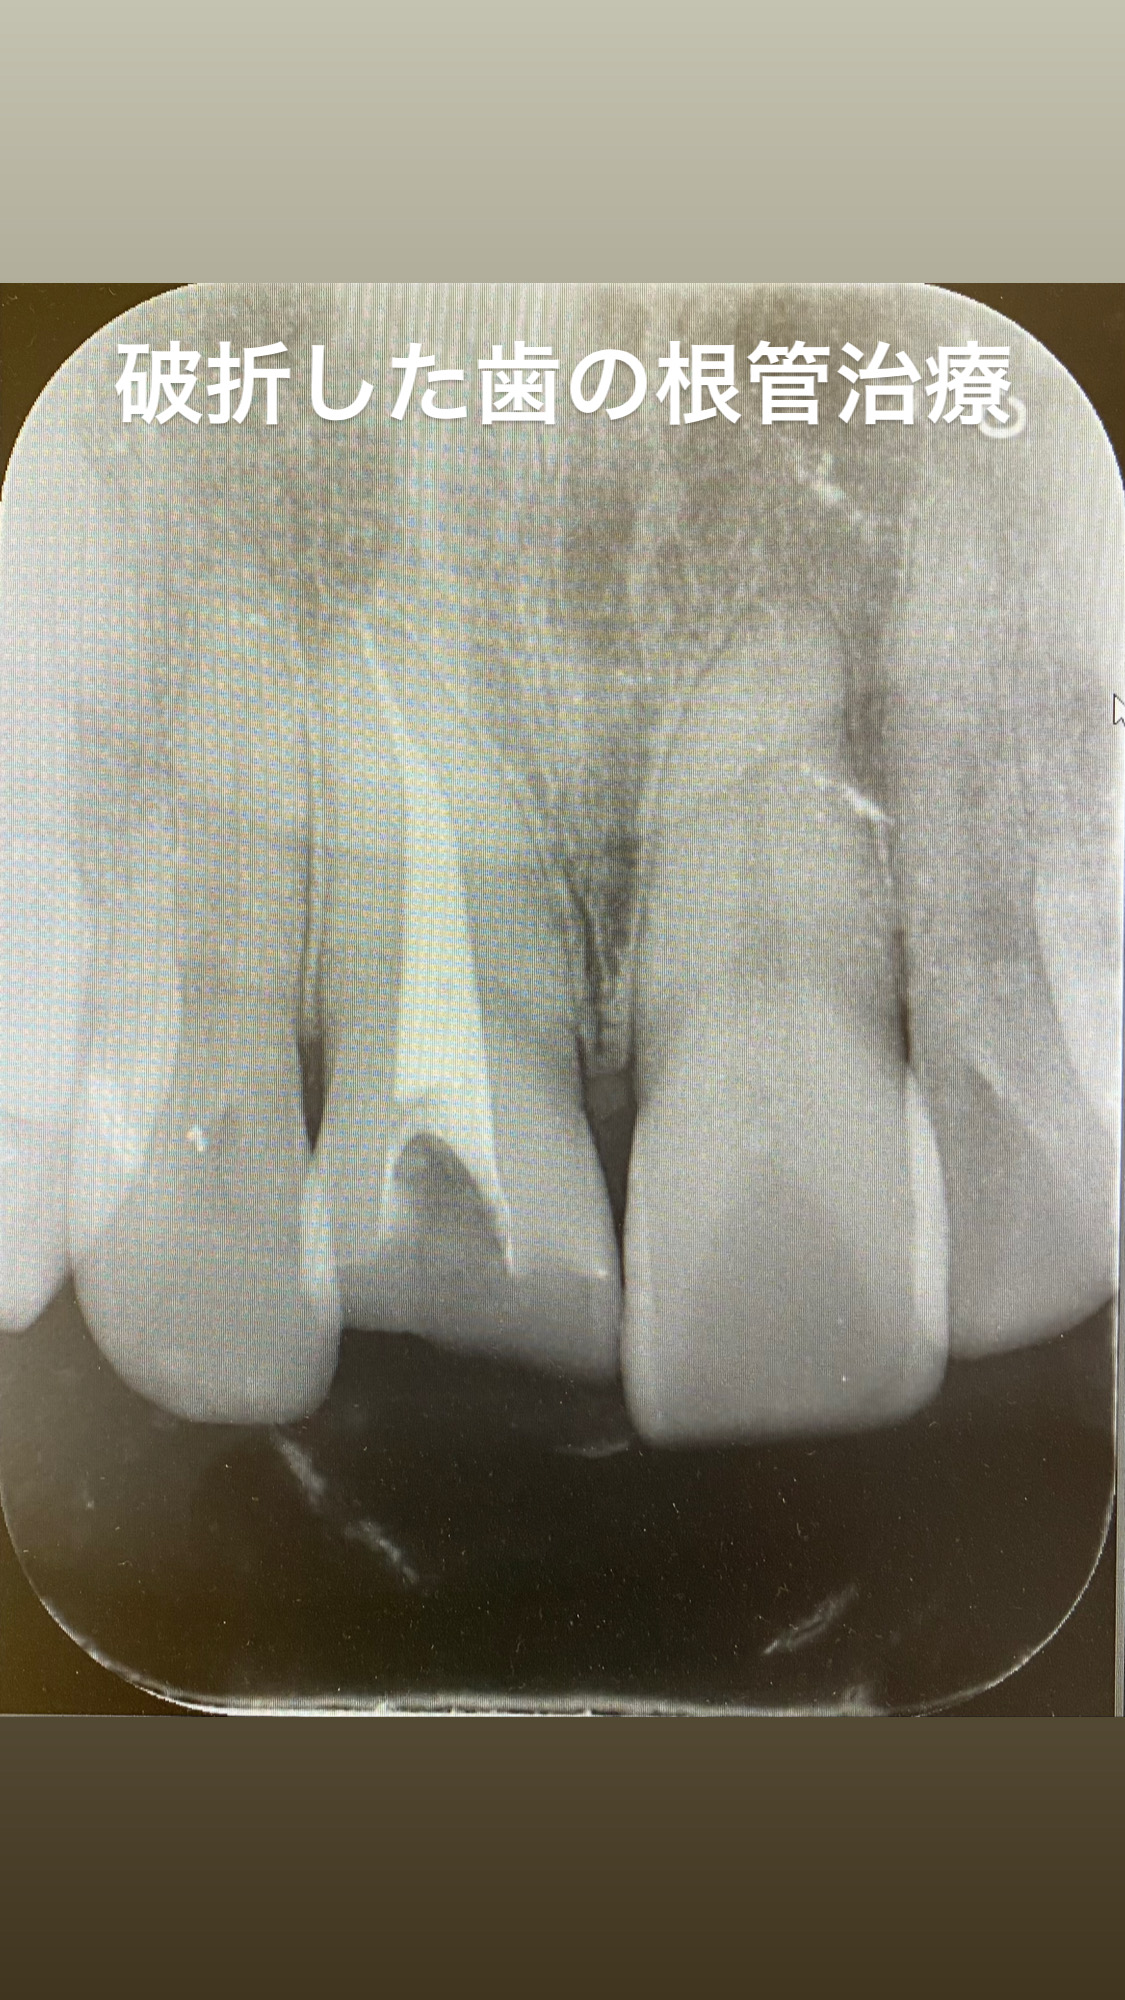

• 根管治療の回数について

根管治療の回数について